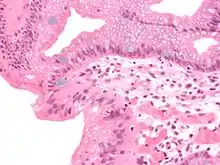

En anatomie pathologique, la métaplasie est la transformation d'un tissu cellulaire différencié en un autre tissu cellulaire différencié. Il s'agit d'un phénomène adaptatif et réversible qui se produit le plus souvent en réponse à une agression tissulaire répétée et prolongée (inflammation, irritation mécanique ou chimique, infection), le tissu de remplacement étant mieux armé que le tissu original contre ladite agression.

Dans la métaplasie, la structure et la fonction du nouveau tissu sont strictement normales, ce qui la distingue de la dysplasie (ou état précancéreux), bien qu'elle puisse évoluer secondairement vers ce stade si l'agression persiste.

La métaplasie ne peut être affirmée que par l'examen microscopique d'un prélèvement tissulaire. En pathologie humaine on la rencontre principalement dans quatre situations :